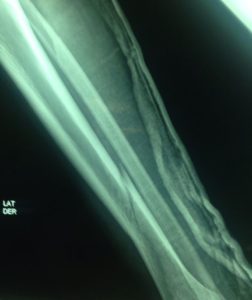

El tratamiento de las fracturas pediátricas ha evolucionado en las últimas décadas, y muchas lesiones que antes se manejaban de manera no quirúrgica ahora se están tratando quirúrgicamente. La Academia Estadounidense de Cirujanos Ortopédicos ha desarrollado pautas clínicas para ayudar a guiar la toma de decisiones y agilizar la atención al paciente para ciertas lesiones, pero muchos temas siguen siendo controvertidos *2, es importante que acudas con un experto, te dará la mejor opinión sobre los problemas del sistema músculo-esquelético de tu pequeño!!!